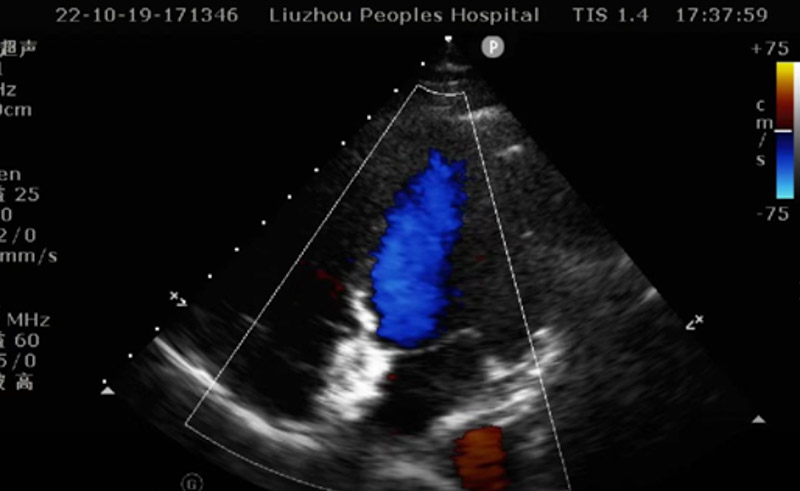

手術(shù)如期進行,心臟外科、超聲科團隊共同協(xié)作,在超聲引導(dǎo)下順利將封堵傘精準通過卵圓孔未閉處,釋放封堵傘,完美封堵缺口。術(shù)后幾日,患者便痊愈出院。